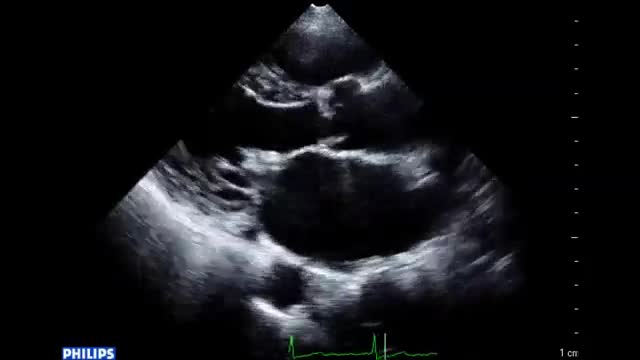

• 図4 心エコー図、手術所見 a

• 図5 心エコー、手術所見 a

図4 心エコー図、手術所見 a